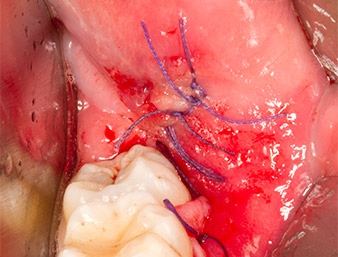

Subsequently, the autogenous bone tissue (Fig. 13) was placed into the alveole and the surrounding bone defect (Fig. 14). Collagen fleece covered the bone chips up to bone level as protection for the exposed nerve (Fig. 15). Sutures using vicryl thread, USP 4.0, were used to close the opened up soft tissue (Fig. 16). An Ibuprofen preparation (Seractil 400 mg, 3x1) and an antibiotic consisting of amoxicillin and clavulanic acid (Augmentin 1 g, 2x1) were prescribed postoperatively.